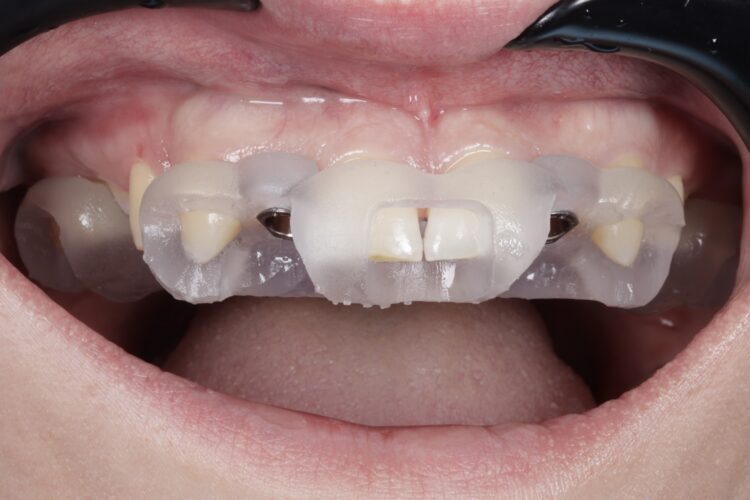

The implant surgery was performed in May 2023 and was filmed live as part of a surgical demonstration for the delegates on a guided surgery course being run by the Fitz Fahey Academy. Implants were placed in the UR2 and UL2 spaces with simultaneous hard and soft tissue grafting. Following the surgery, the patient was provided temporary teeth and instructed to avoid putting undue pressure on the implants during healing.